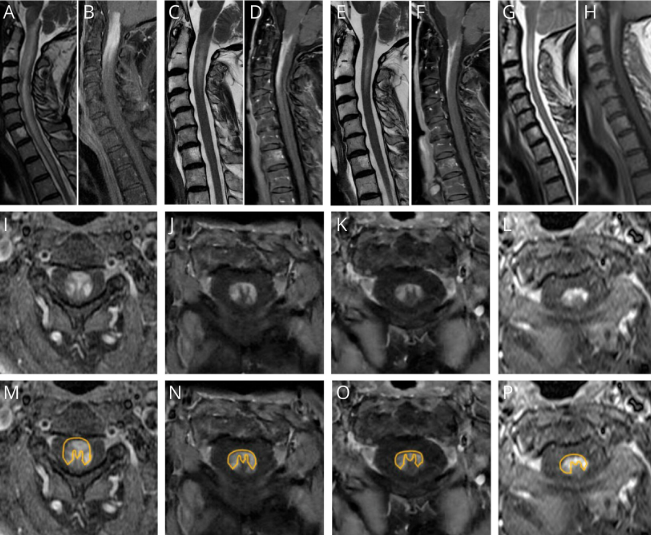

Delighted to share Cacciaguerra et al study ➡️ MRI guidelines in MS recommend 2 sagittal-T2 spine images but axial is optional ➡️ Here, axial-T2 found 2x more lesions vs sagittal ➡️ Thus, future guidelines should recommend both sagittal & axial images👇 link.springer.com/article/10.100…